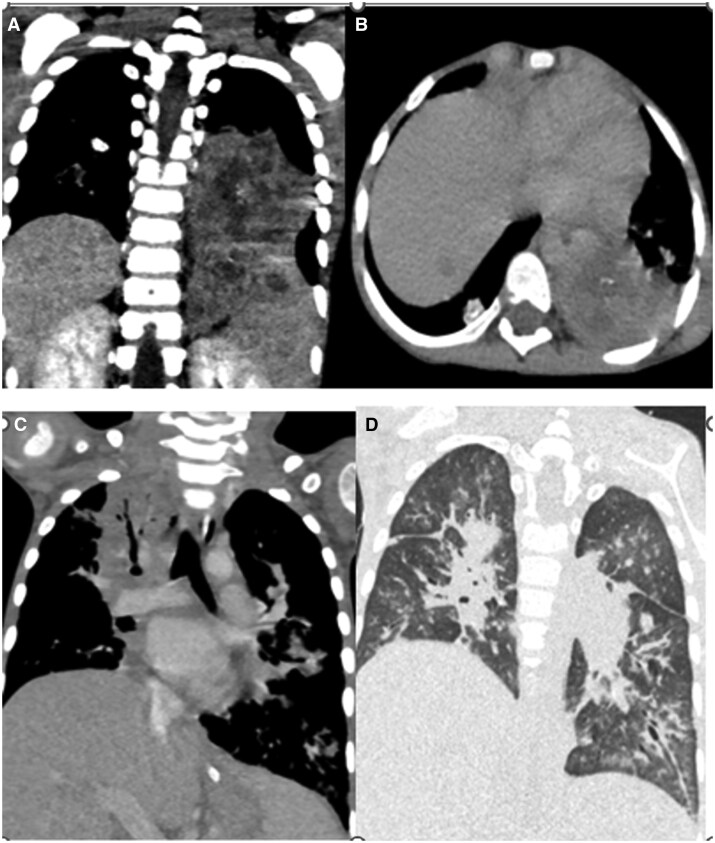

Bronchocentric granulomatosis is a rare form of granulomatous disease characterized by peribronchiolar or peribronchial necrotizing granulomas.1 The imaging findings are non-specific and include nodular or mass-like lesions and pneumonic consolidation.2 We present a case of bronchocentric granulomatosis in a patient with Pre-B-cell acute lymphoblastic leukaemia. The aim of the case report is to make the radiologist aware of this condition and emphasize the importance of multimodality approach which along with clinical findings helps in reaching a diagnosis and managing this rare complication.